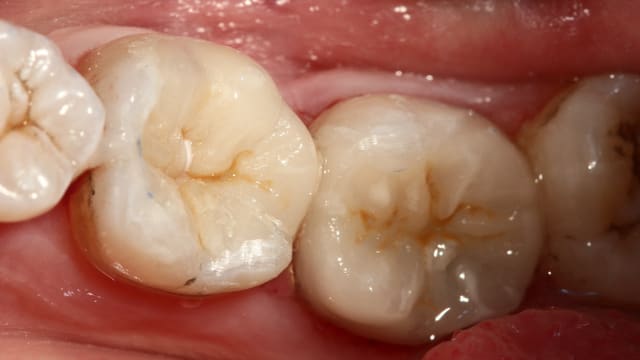

Oune plous pitite ...)))

La 16 est magnifique , le compo de la 4 également (le pan d'émail sert de point de contact , youpi)...

Patient habituel si on peut dire , pris en paro par ma femme , reparti chez un ami...à lui pour les prothèses , reviendu chez moi .

J'ai des bourrages , effectivement c'est ballot et à part refaire les cérams , je ne vois pas .

Pis chuis nul en composite , on va faire un onlay , c'est la seule soluce . Oui je vais en profiter parce que d'ici 2 ans je serai à la retraite , et la moutouelle...là on me rembourse tout . Je vais quand vous faire un devis à tout hasard...)))